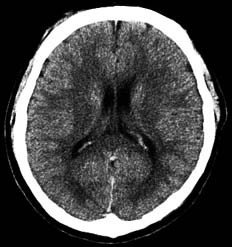

頭部CT

X線を使用する撮影ですが、細いX線ビームを回転しながら出してそれをコンピュータ画像処理したものです。

スライス番号は、すぐ下のCT画像に対応しています。上段の図をクリックすると下段のCT画像が拡大して見られます。